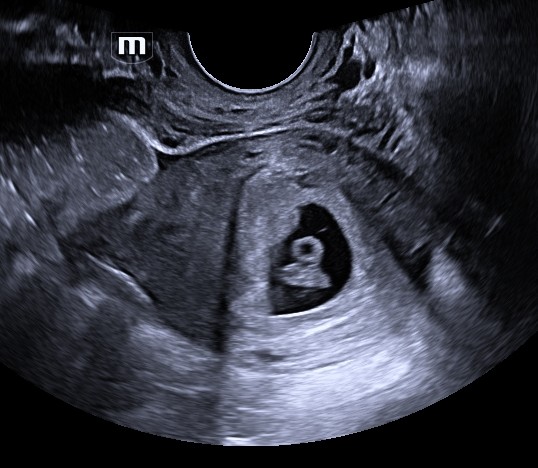

Next, Morgan met with a nurse, Danielle. “She was a fantastic nurse who was very informative, respectful, and kind,” said Morgan. “She took her time explaining things to me, answering any questions I had, and making sure I had the resources I needed.” The ultrasound didn’t provide all the information they needed to confirm viability, so Morgan was asked to return.

When Morgan came back for her second appointment, the baby’s heartbeat was still low. She suggested Morgan come back for another ultrasound a week later to ensure viability. “She made me feel like I was safe walking out of the appointment,” said Morgan. “It was almost like she was holding my hand through all of these unknowns.”

The follow-up ultrasound showed a strong heartbeat and a viable pregnancy. Now, it was time for Morgan and her boyfriend to make a decision.